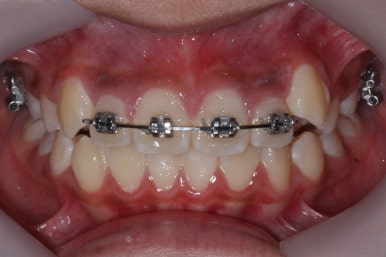

영구치도 이제 거의 다 나왔고 삐뚤한 다른 부분도 전체 메탈장치를 붙였습니다.

장치는 윗니부터 붙였습니다.

입안에 장치가 있다보니 불편할 수 있는데요. 이물감을 최소화 하고자 이동을 해야 할 양이 적은 아랫니들은 천천히 장치를 붙이기로 했습니다.

아래쪽에도 이제 장치를 전부 부착했습니다.

한 쪽의 송곳니는 제위치로 벌써 자리를 잡았네요.

장치를 부착한 후에 순차적으로 변화가 나타나는 모습입니다.

총 4장의 사진 동안 경과한 시간은 불과 6개월 입니다. 헤드기어를 통해 사전에 작업을 해뒀기 때문에 이후 연산동덧니교정 과정은 편해진 것이죠.